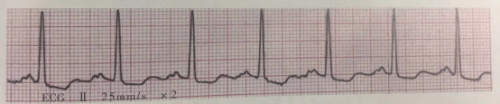

4.陣發(fā)性室上性心動過速的心電圖表現(xiàn)

(1)相當(dāng)于一系列連續(xù)很快的房性或交界性早搏,頻率150~250/分,節(jié)律規(guī)則。

(2)QRS波群形態(tài)基本正常,時間≤0.10s。

(3)ST-T無變化,或發(fā)作時S-T段下移和T波倒置。